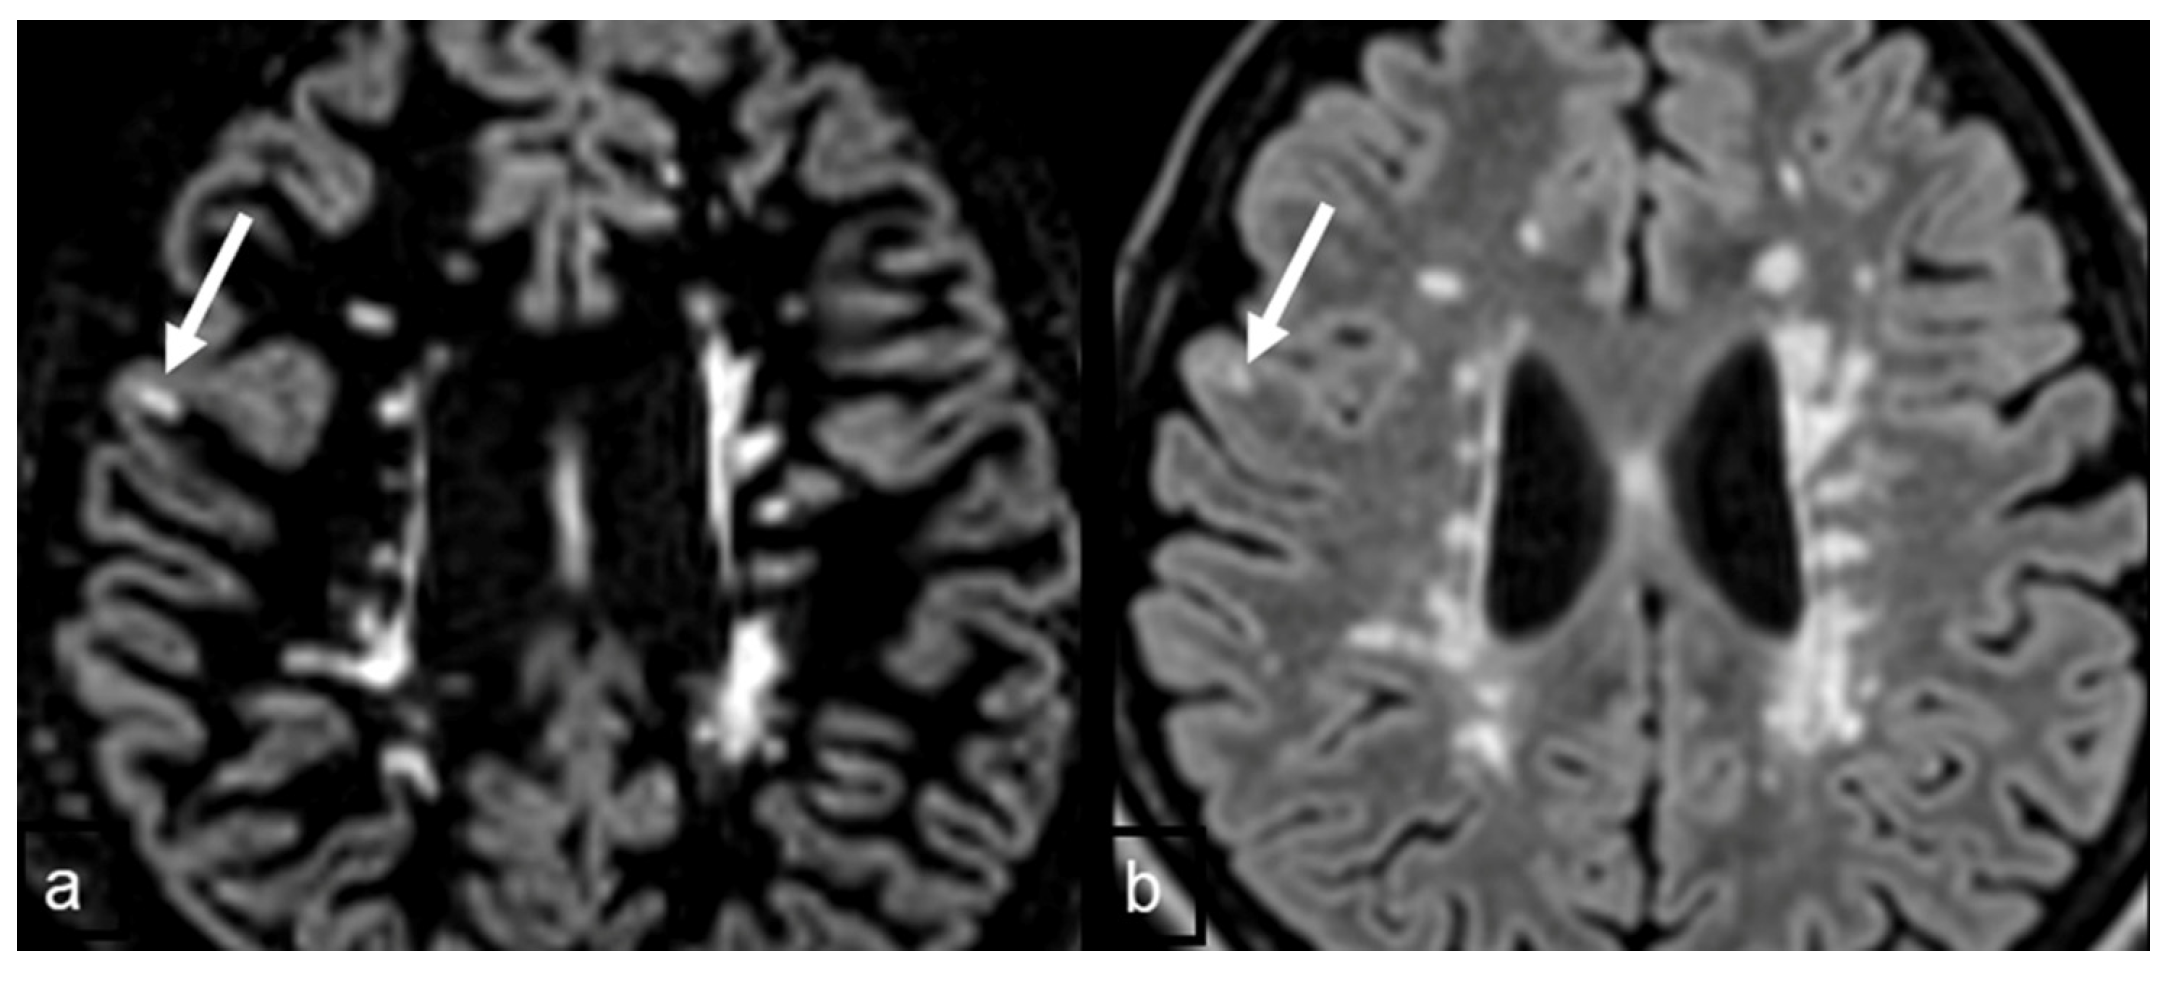

| Practical Recommendation |

| In MS protocol, attention has to be paid to perform DIR before contrast-administration, as post-contrast DIR may suppress active subcortical lesions. |